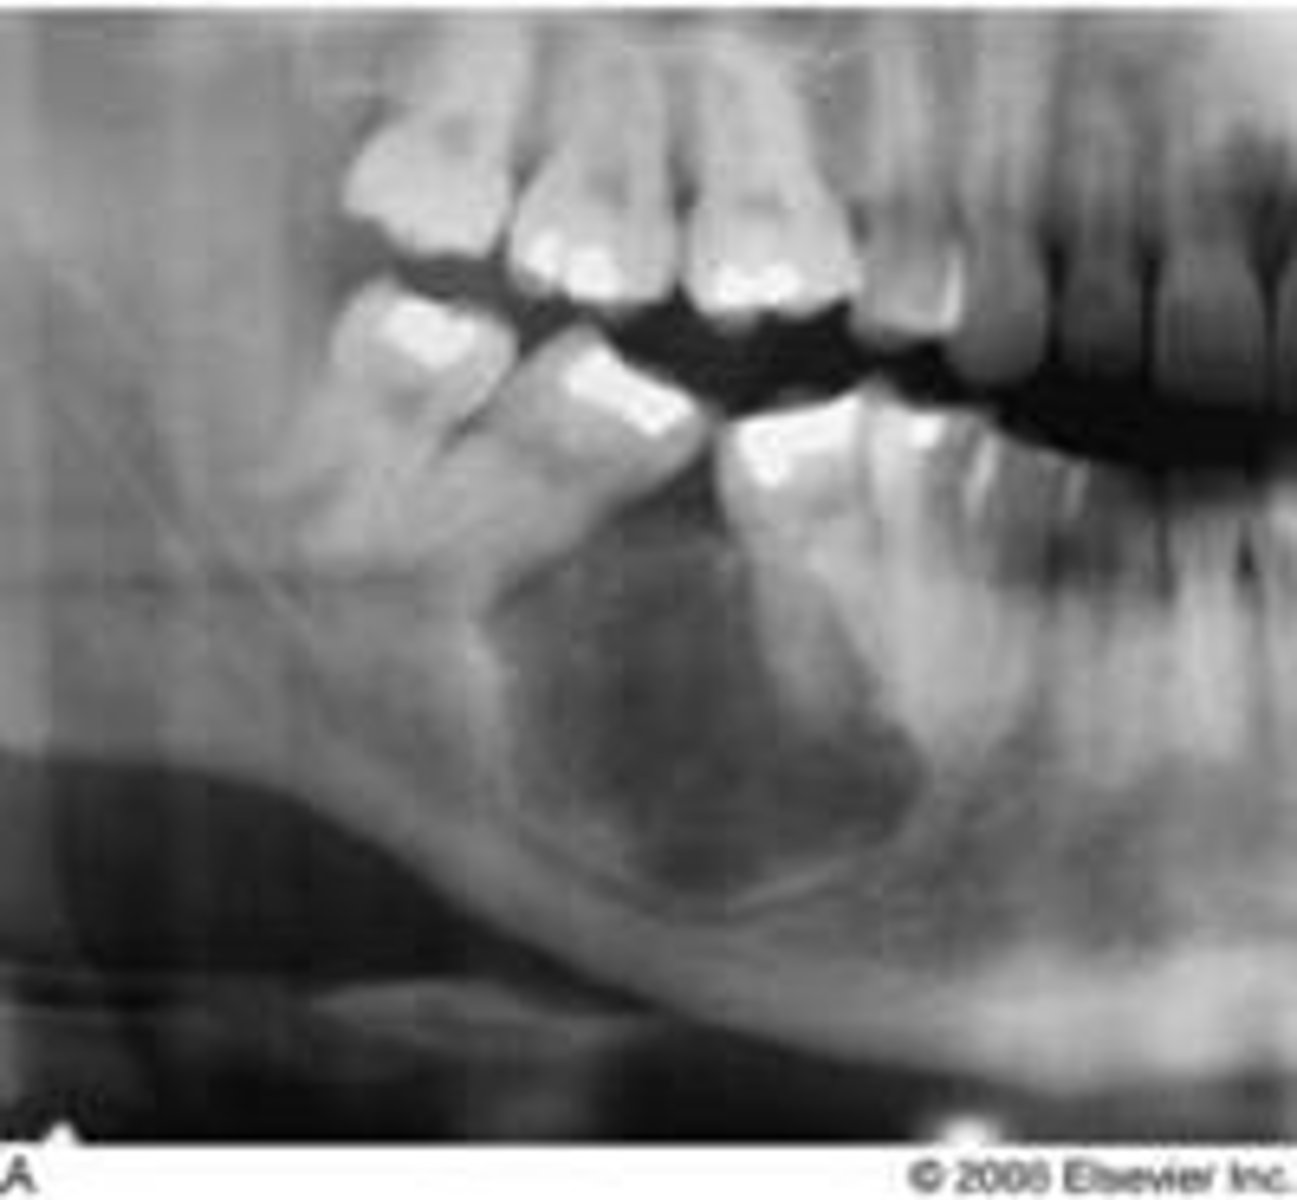

what is an odontogenic keratocyst / keratocystic odontogenic tumor **

it is a benign cyst but it can grow to be super aggressive; ass/ w Gorlin SX/NevoidBCCSx

OKC (+ common location, associations/radiographic appearance, population)

common locations: posterior mandible

clinical features: asymptomatic; displacement and resorbs teeth structure

radiographic: well-defined uniocular (when small)/multiiocular radiolucency

population: young adults 20-30s; males